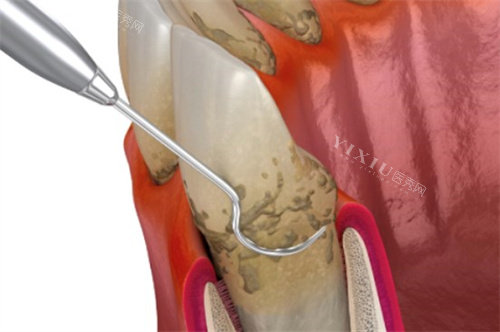

为啥不能一次全口大扫除?

很多人躺上牙椅就琢磨:打都打麻药了,干嘛不一次全刮完省事?这想法挺实在,但牙医坚持分次治,背后全是硬道理。

•嘴巴扛不住啊!张着嘴一动不动,时间长了腮帮子又酸又累。

刮治时那些小工具在敏感的牙根上仔细清理,时间拖太久,你难受,医生也难保精细操作。

•发炎牙龈太娇气。

尤其是肿得出色的牙龈,特别脆弱。

如果不管不顾一次猛刮,疼得出色不说,还可能让炎症更嚣张。

分几次来,让发炎的地方缓一缓,下次再处理就顺利多了。